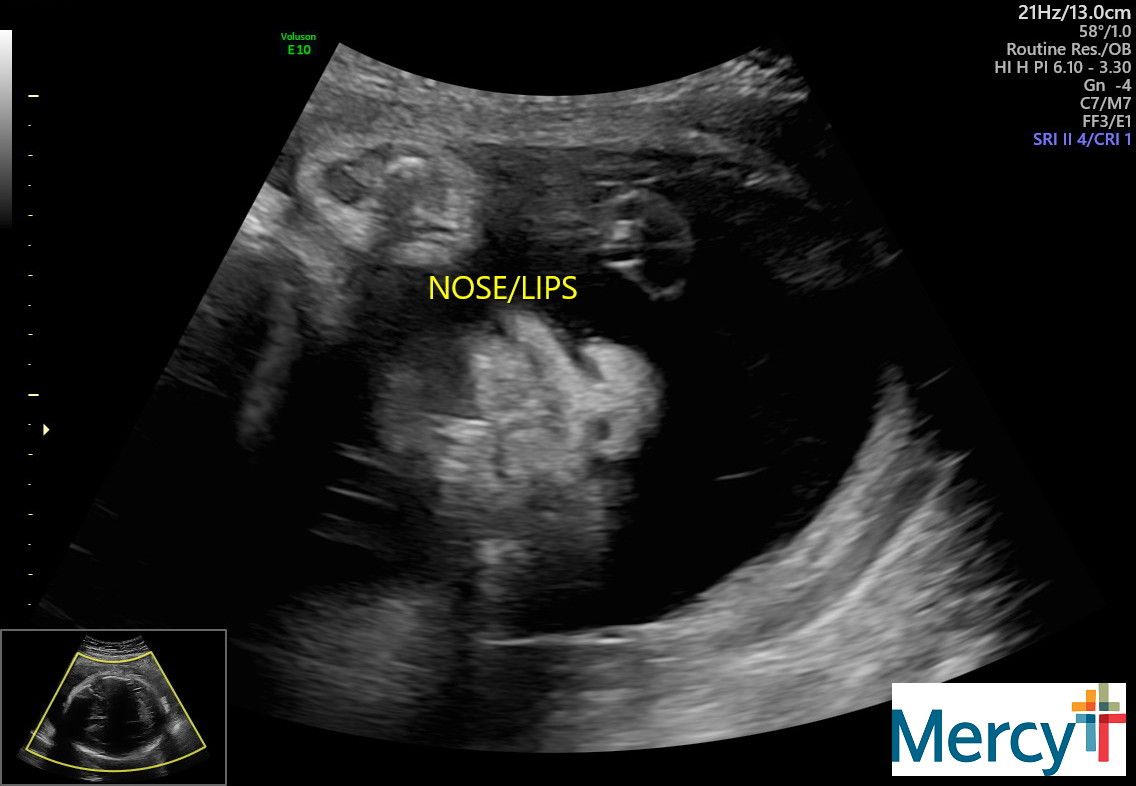

At 32 weeks my appointments would change from once a week to twice a week. These appointments would have a NST (non-stress test) and an ultrasound to check my anniotic fluid levels.

Lupus pregnancies are so complex. The placenta ages rapidly near the end and risk for stillbirth is so high.